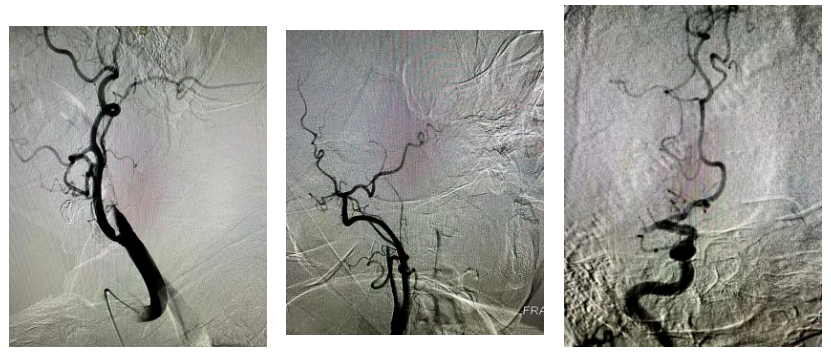

经股动脉穿刺置鞘,造影管依次行主动脉弓、双侧颈动脉、椎动脉造影——术中明确了“罪魁祸首”:右侧颈内动脉颅内段闭塞、右侧大脑中动脉闭塞。这两处关键血管的堵塞,正是导致老人意识障碍、肢体瘫痪的主要原因。

取栓过程同样步步惊心。手术团队操控超滑导丝,将长鞘精准送至右侧颈内动脉C1段,再引导微导管、微导丝穿过闭塞段,抵达右侧大脑中动脉M2段。确认位置无误后,取栓支架精准释放,牢牢嵌合血栓。

负压抽吸、回收支架——当支架取出的瞬间,一段约10mm的血栓被成功带出!

13:40,首次复查造影显示,右侧大脑中动脉血流完全再通;10分钟后再次复查,远端血管显影良好,脑实质、静脉期均无异常。13:50,顺利完成了这场高难度的高龄取栓攻坚战。